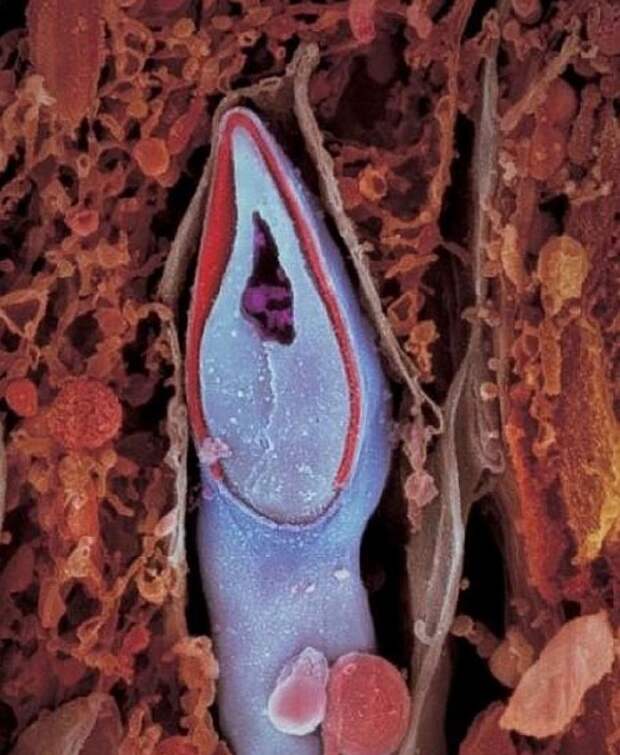

5. Сперматозоид в разрезе. В головке содержится весь генетический материал.